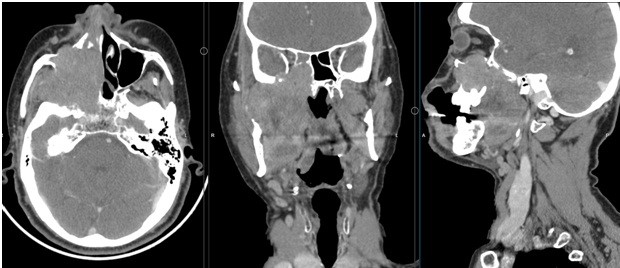

Impact of induction chemotherapy on resectability of borderline resectable/unresectable oral cavity carcinomas

Induction chemotherapy in borderline resectable oral cavity cancers

L.K. Rajeev , Dayananda Sagar P, K.N. Lokesh, Chetan V, A.H. Rudresh, G.V. Giri, Smitha C Saldanha, Yaman Patidar, Suresh Babu